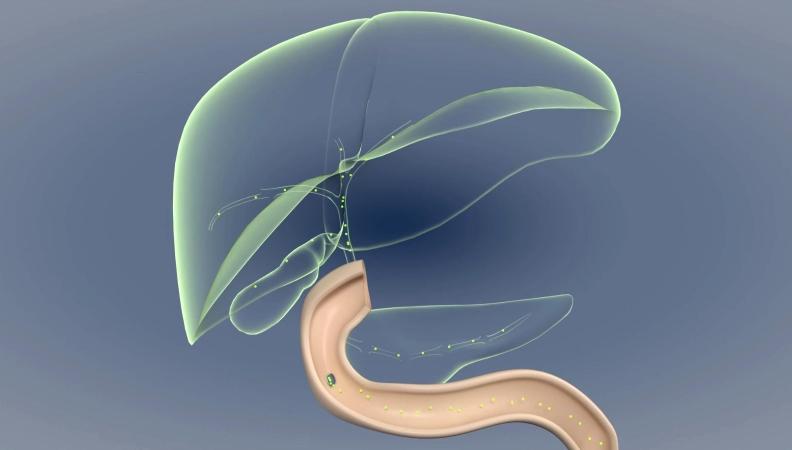

科技新突破丨我國科學(xué)家揭示膽汁淤積瘙癢的分子機(jī)制